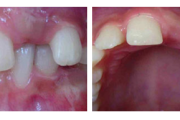

Laste ja noorukite söömishäired. Anorexia nervosa, Bulimia nervosa